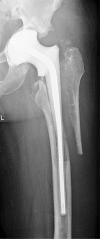

Two-stage revisions with antibiotic-loaded spacers have gained popularity for treating infected hip-joint arthroplasties. The aim of this prospective study was to assess patient functionality between stages and treatment impact on duration of hospital stay and to describe related complications. Sixty-one consecutive patients with infected hip arthroplasties underwent two-stage revision with preformed spacer implantation. Mean Harris Hip and Merle d'Aubigné scores between the two stages were 39.9 and 7.6, respectively. Forty-six patients (75.4%) were able to leave hospital between stages. Spacer dislocation occurred in 16.4%. No cases of spacer breakage were noted. Preformed cement spacers provide acceptable functional outcome between revision hip arthroplasty stages and facilitate the surgical procedure without increasing mechanical complication rates.